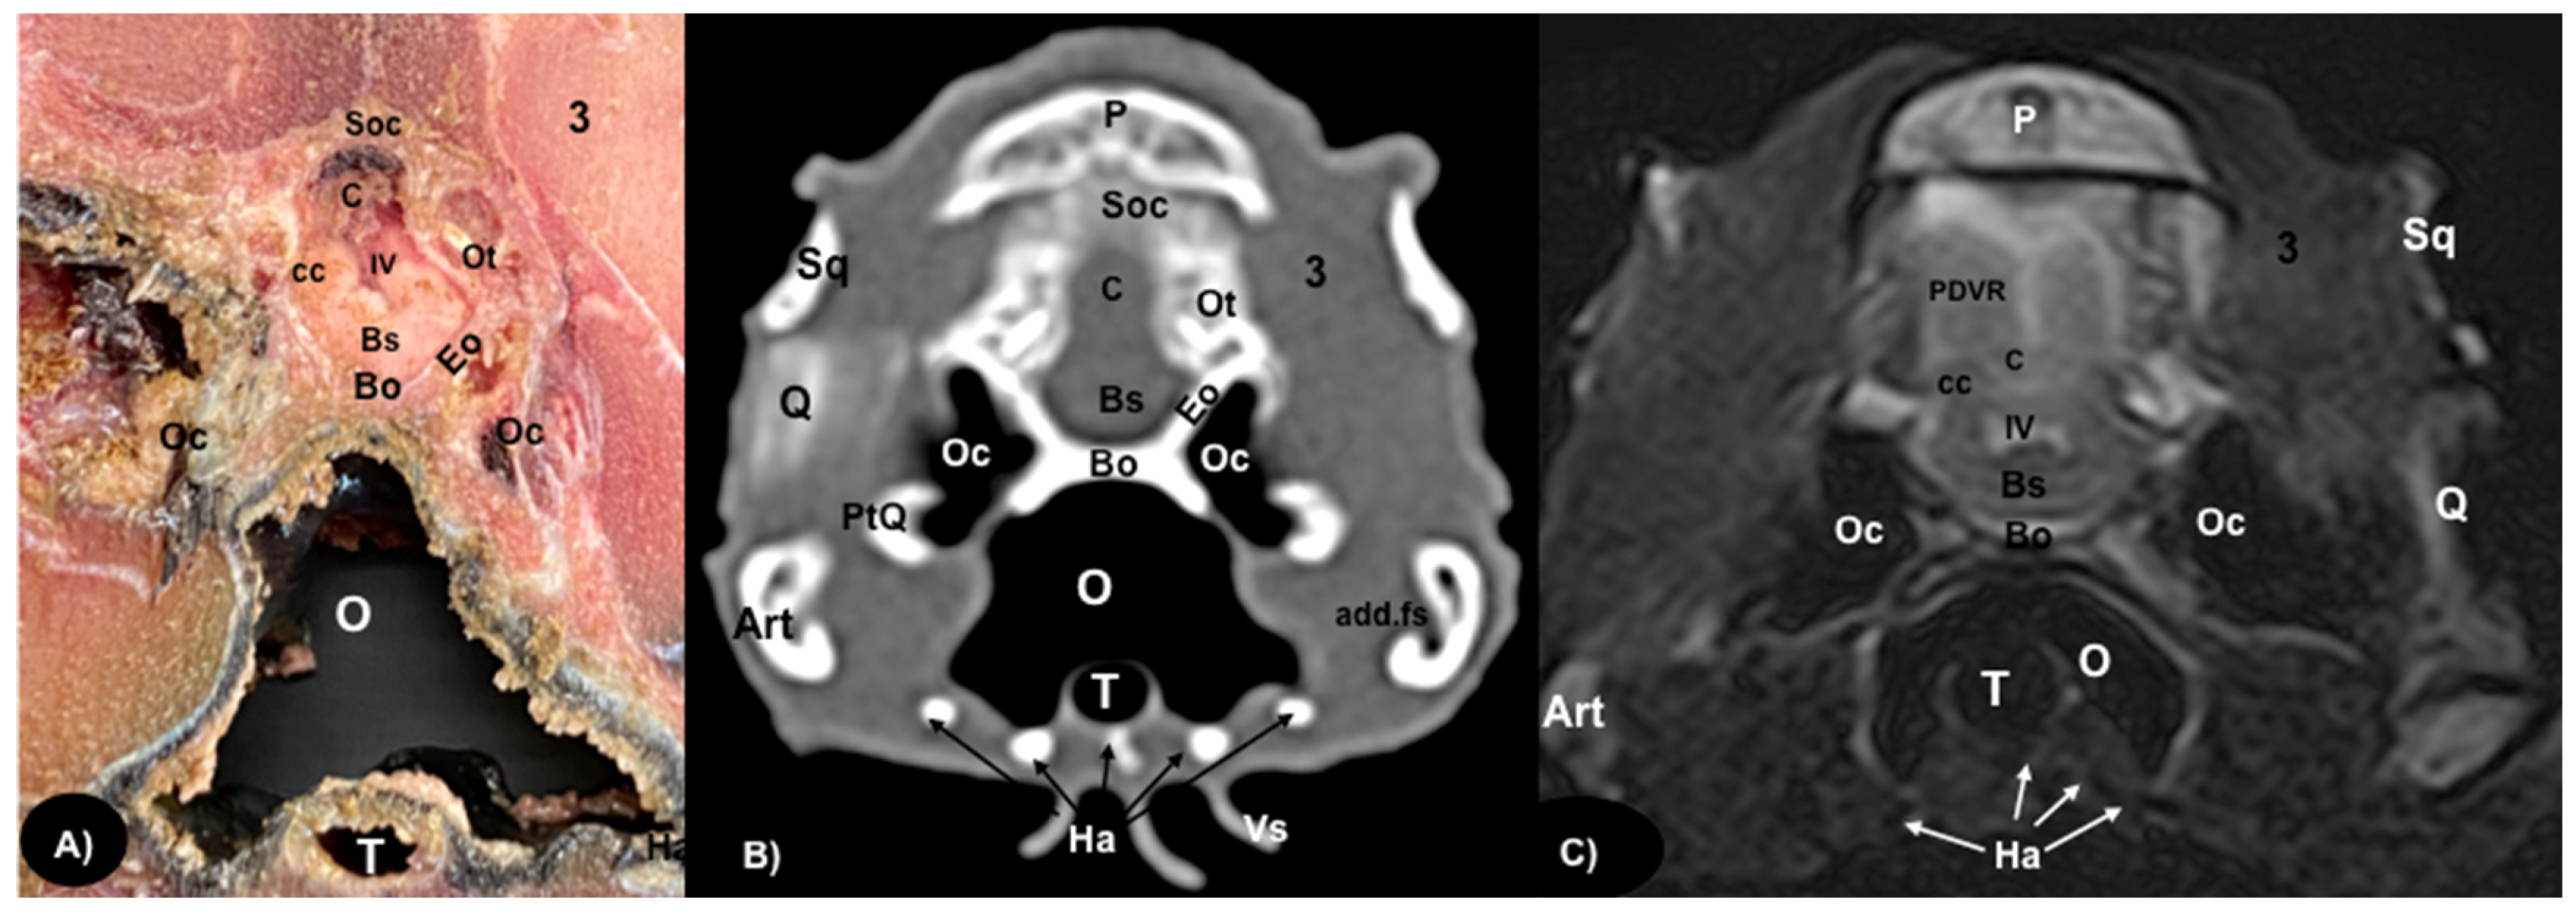

Figure 6.

Transversal gross-section (A), CT bone window (B) and MRI in T2W (C), images of the head of rhinoceros iguana at the level of the occipital region corresponding to line V in Figure 1. P: Parietal bone. Soc: Supraoccipital bone. Sq: Squamosal bone. 3: Musculus adductor mandibulae externus superficialis. C: Cerebellum. PDVR: Posterior Dorsal Ventricular Ridge. Bs: Brain stem. cc: Caudal colliculus. IV: Fourth ventricle. Ot: Otoccipital bone. Eo: Exoccipital bone. Bo: Basioccipital bone. Oc: Otic cavity. Q: Quadrate bone. PtQ: Pterygoid-quadrate processes. Art: Articular bone. add.fs: Adductor fossa. O: Oral cavity. T: Trachea. Ha: Hyoid apparatus. Vs: Ventral spines.

Different structures belonging to the central nervous system were visualized by anatomical gross-sections. Therefore, we identified the brain (telencephalon) and the two telencephalic hemispheres (Figure 4A and Figure 5A) separated by the fissura longitudinalis cerebri (Figure 5A), the diencephalon (thalamus) (Figure 4A and Figure 5A), the dorsal part of the mesencephalon with the two caudal colliculus (Figure 6A) and the ventral part of the cerebellum with the nodule, covering part of the fourth ventricle, as well as the ventral surface of the brainstem (myelencephalon) (Figure 6A). These sections were also helpful for the observation of the olfactory bulb that showed an extracranial location, ventral to the frontal bones, and coursed between the two eyeballs (Figure 3). In addition, these sections allowed the description of structures of the eyeball, identifying the cornea, the sclera, the retina, the vitreous humor, the lens, as well as associated structures such as the interorbital septum and the orbital sinus (Figure 3A and Figure 4A). In addition, these transverse sections allowed the identification of structures belonging to the oral cavity such as the tongue (Figure 2A) and other structures such as the larynx, with the corniculate tubercles of the arytenoid cartilage, the thyroid cartilage, and the laryngeal ventricle (Figure 3A), as well as of different structures of the nasal cavity such as the nasal glands that filled almost the entire cavity, the conchal grooves and the stammteil located laterally to the nasal septum (Figure 2A). Adjacent structures such as the trachea and the nasopharynx were also well identified (Figure 4A, Figure 5A and Figure 6A). Furthermore, most bony structures that form the neurocranium were observed, such as the pterygoid, frontal, postfrontal-postorbital, parietal, supraoccipital, basioccipital, exoccipital, otoccipital, parabasisphenoid and sphenoid bones (Figure 3A, Figure 4A, Figure 5A and Figure 6A), as well as those that form the splanchnocranium such as the nasal, vomer, palatine and maxillary bones (Figure 2A and Figure 3A) and also the medial horn located dorsal to the nasal bone (Figure 2A), the mandible, with the dentary bone (Figure 3A), and the hyoid apparatus, visualizing the central body of the hyoid arch, between the lateral branches of the dentary bone (Figure 3A). Rostromedially to the two dentary bones, we identified different muscles related to the hyoid apparatus such as the musculus genihyioideus, hyoglossus and intermandibularis (Figure 2A and Figure 3A). In the following sections, we also observed the muscle groups corresponding to the mandibular musculature (we were not able to dissect them, and therefore they were treated as a group), including the pterygoideus, omohyoideus, sternohyoideus, ceratohyoideus, adductor mandibulae externus medialis and its homonym superficialis (Figure 4A and Figure 5A).

Regarding the neurocranium, the CT images allowed us to distinguish bone structures such as the prefrontal, frontal, postfrontal-postorbital, parietal, squamosal, quadrate, epipterygoid, pterygoid, basioccipital, exoccipital, otoccipital and parabasisphenoid bones (Figure 3B, Figure 4B, Figure 5B and Figure 6B); related to the splanchnocranium, we observed the nasal, premaxilla, maxilla, septomaxilla, vomer, jugal and palatine bones, and the nasal septum (Figure 2B, Figure 3B, Figure 4B, Figure 7B and Figure 8B); the mandible structures such as the dentary, angular, surangular, coronoid and articular bones (Figure 2B, Figure 3B, Figure 4B, Figure 5B and Figure 6B) and the hyoid apparatus (Figure 2B, Figure 3B, Figure 4B, Figure 5B and Figure 6B). CT scanning and post-processing transverse images showed the relation between the different bones that form the head of the rhinoceros iguana, the junction of the nasal and the prefrontal bone, as well as that of the parietal bone with the postfrontal-postorbital bone (Figure 2B and Figure 4B), and the palatine and quadrate processes of pterygoid bone (Figure 5B and Figure 6B respectively). The prominent medial horn was identified dorsal to the nasal bone with soft-tissue attenuation and a thin, lamellar-shaped mineral structure bordering it regularly on its most external aspect (Figure 2B).

Concerning the nasal cavity, the transverse CT image showed the nasal glands as symmetrical bilateral structures, with regular and well-defined margins, located on both sides of the nasal cavity and with soft tissue attenuation (Figure 2B). Moreover, those structures with intraluminal gas content such as the nasal conchal recess (Figure 2B), oral cavity, nasopharyngeal duct, trachea, adductor fossa (Figure 4B) and the otic cavity (Figure 6B) were identified with this technique, appearing with a vacuum effect. In addition, there were areas of soft tissue attenuation medial to the mandible and bilateral to the hyoid apparatus, compatible with the intermandibularis, genihyioideus and hyoglossus muscles (1 in Figure 2B and Figure 3B), the pterygoideus, omohyoideus, sternohyoideus and ceratohyoideus muscles (2 in Figure 4B), the adductor mandibulae externus medialis and superficialis muscles located, respectively, dorsomedially and ventrolaterally to the adductor fossa (3 and 4 in Figure 4B and Figure 5B).

3.3. Magnetic Resonance Imaging (MRI)

The soft structures of the iguana’s head, such as the central nervous system as well as the eyeball’s structures (vitreous humor and lens), the oral cavity with the tongue and the masticatory muscles, showed an accurate visualization using MRI (Figure 2C, Figure 3C, Figure 4C, Figure 5C and Figure 6C). Therefore, an increased volume of both eyeballs in proportion to the size of the head was seen in all sequences (Figure 3C and Figure 7B). As in CT, the structures with gas content (Figure 2C and Figure 6C) appeared with a vacuum effect, being hypointense in all sequences. The nasal glands were bilaterally symmetric, with regular and well-defined margins, located on both sides of the nasal cavity, being iso/hyperintense in T1W and T2W sequences, compared to the encephalic grey matter (Figure 2C and Figure 4C). In contrast, the medial horn appeared hypo/isointense on T1W and T2W sequences concerning the white matter and with mild differentiation of the external bony cortex in relation to the white matter (Figure 2C).

In contrast to the CT images, the bone junctions were not distinguishable on MRI, but those bones that formed the neurocranium, such as the frontal, postfrontal-postorbitary, parietal and supraoccipital bones were identified (Figure 3C, Figure 4C, Figure 5C, Figure 6C and Figure 8B). The cranial musculature was found isointense concerning the thalamus in T2W. This technique enabled a better resolution to identify the muscle groups already mentioned (Figure 2C, Figure 3C, Figure 4C and Figure 5C). In the transverse planes of the encephalon, the cerebral cortex was observed slightly more hyperintense than the white matter, which was more hypointense in T2W sequences (Figure 4C). The diencephalic region (Figure 4C, Figure 5C and Figure 8B) was hypointense (T2W) compared to the cerebral cortex (Figure 5C), showing the thalamus and hypothalamus (Figure 8B). The brainstem appeared hypo/isointense in T2W compared to the cerebral cortex, as well as presenting a markedly tortuous horizontal alignment (Figure 8B). Moreover, the caudal colliculus and the fourth ventricle were also displayed in excellent detail. In the rostral aspect of the telencephalon, we distinguished the dorsal pallium rostral part with its lateral and medial portions (Figure 4C). Interestingly, the dorsal MRI image was quite helpful to identify the olfactory bulb located extracranially, which extended rostromedially between the eyeballs (Figure 3C, Figure 7B and Figure 8B).